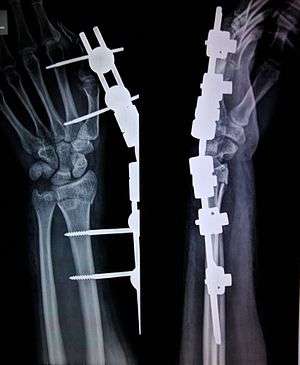

External fixation is a surgical treatment used to stabilize bone and soft tissues at a distance from the operative or injury focus. They provide unobstructed access to the relevant skeletal and soft tissue structures for their initial assessment and also for secondary interventions needed to restore bony continuity and a functional soft tissue cover.

The parts of an external fixator include:

1. Schanz pin

2. Connecting rods

3. Clamps.

In this kind of reduction, holes are drilled into uninjured areas of bones around the fracture and special bolts or wires are screwed into the holes. Outside the body, a rod or a curved piece of metal with special ball-and-socket joints joins the bolts to make a rigid support. The fracture can be set in the proper anatomical configuration by adjusting the ball-and-socket joints. Since the bolts pierce the skin, proper cleaning to prevent infection at the site of surgery must be performed.